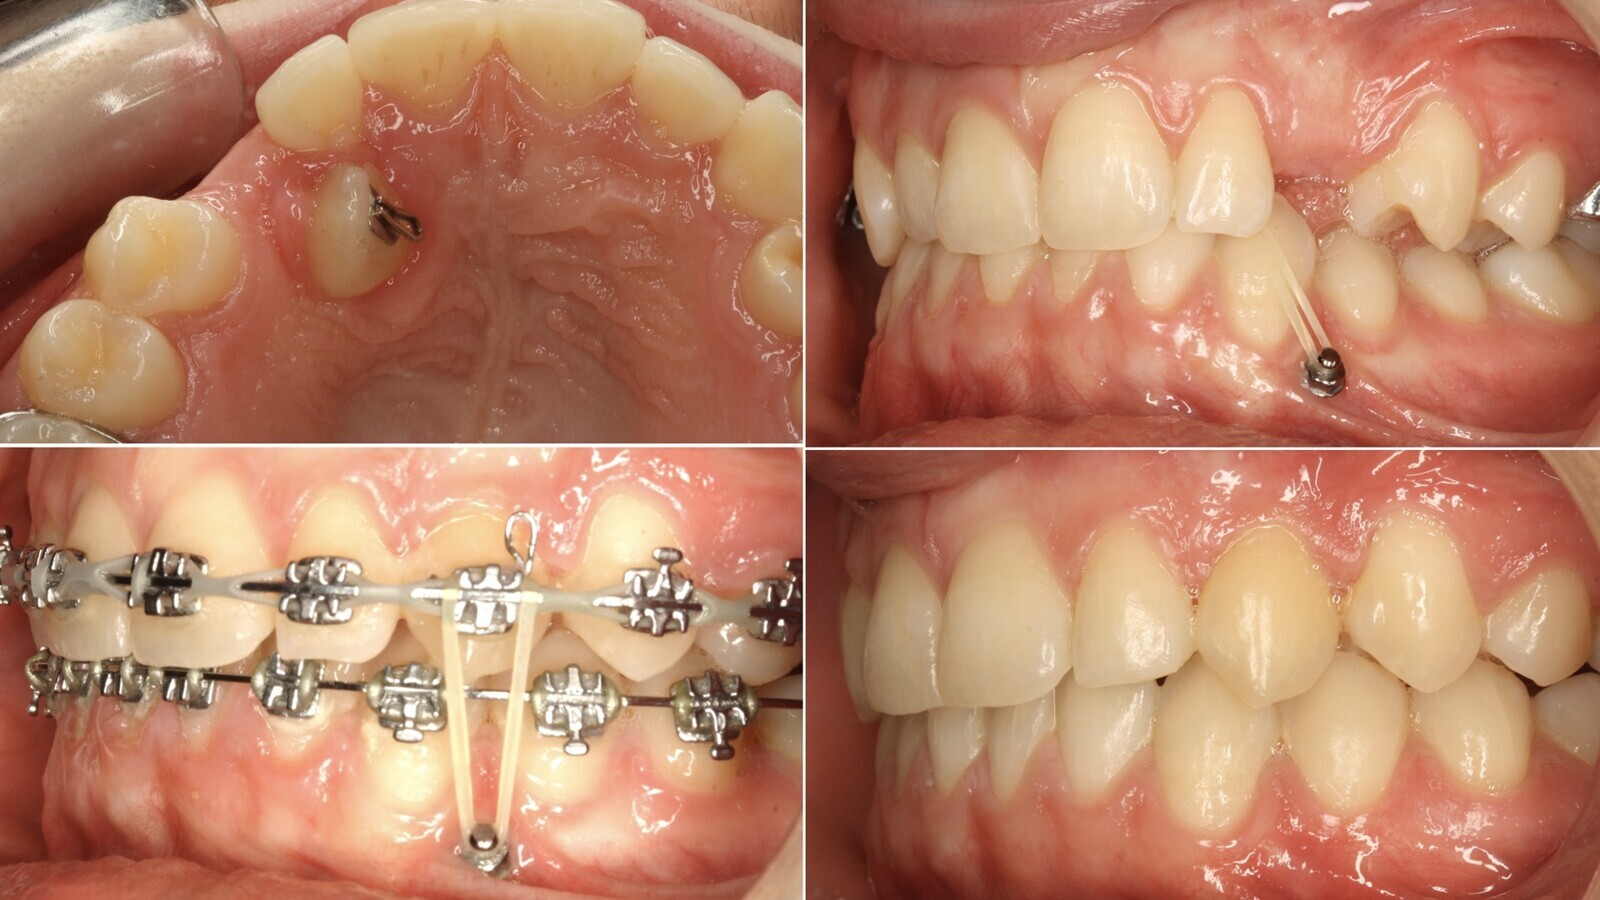

6. Los Microimplantes son un excelente anclaje, seguro, indoloro, confortable y económico, para la tracción ortodóncica inicial de los caninos (figuras 14, 15 y 16).

Figuras 14, 15 y 16. Los Microimplantes son un excelente anclaje, seguro, indoloro, confortable y económico, para la tracción ortodóncica inicial de los caninos.